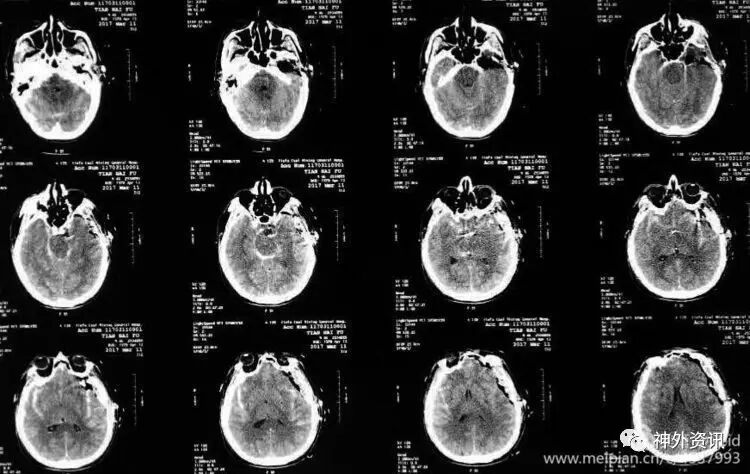

术后复查头CT显示手术效果满意。

术后第2天病人神志转清,四肢可以自主活动。